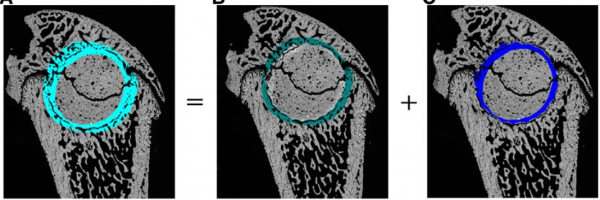

动物步态分析系统的创新应用 →骨损伤修复重建中疼痛问题的研究

本文的意义在于开创了一个用来评价骨重建修复引起的疼痛的指导方法:CatWalk步态分析系统的行为直观测试方法,这对该领域的研究起到指导和借鉴作用。